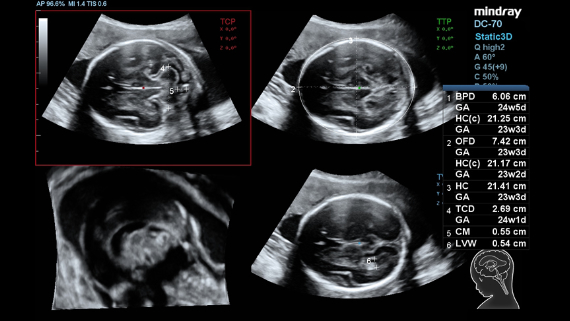

ImĂĄgenes clĂnicas